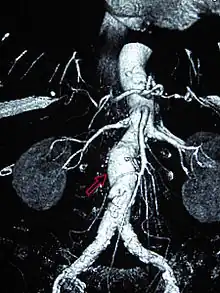

Abdominal

Abdominal aortic aneurysms (AAAs) are more common than their thoracic counterpart. One reason for this is that elastin, the principal load-bearing protein present in the wall of the aorta, is reduced in the abdominal aorta as compared to the thoracic aorta. Another is that the abdominal aorta does not possess vasa vasorum, the nutrient-supplying blood vessels within the wall of the aorta. Most AAA are true aneurysms that involve all three layers (tunica intima, tunica media and tunica adventitia). The prevalence of AAAs increases with age, with an average age of 65–70 at the time of diagnosis. AAAs have been attributed to atherosclerosis, though other factors are involved in their formation.[7]

The risk of rupture of an AAA is related to its diameter; once the aneurysm reaches about 5 cm, the yearly risk of rupture may exceed the risks of surgical repair for an average-risk patient. Rupture risk is also related to shape; so-called "fusiform" (long) aneurysms are considered less rupture-prone than "saccular" (shorter, bulbous) aneurysms, the latter having more wall tension in a particular location in the aneurysm wall.[9]

Before rupture, an AAA may present as a large, pulsatile mass above the umbilicus. A bruit may be heard from the turbulent flow in the aneurysm. Unfortunately, however, rupture may be the first hint of AAA. Once an aneurysm has ruptured, it presents with classic symptoms of abdominal pain which is severe, constant, and radiating to the back.[9]

The diagnosis of an abdominal aortic aneurysm can be confirmed by the use of ultrasound. Rupture may be indicated by the presence of free fluid in the abdomen. A contrast-enhanced abdominal CT scan is the best test to diagnose an AAA and guide treatment options.[10]